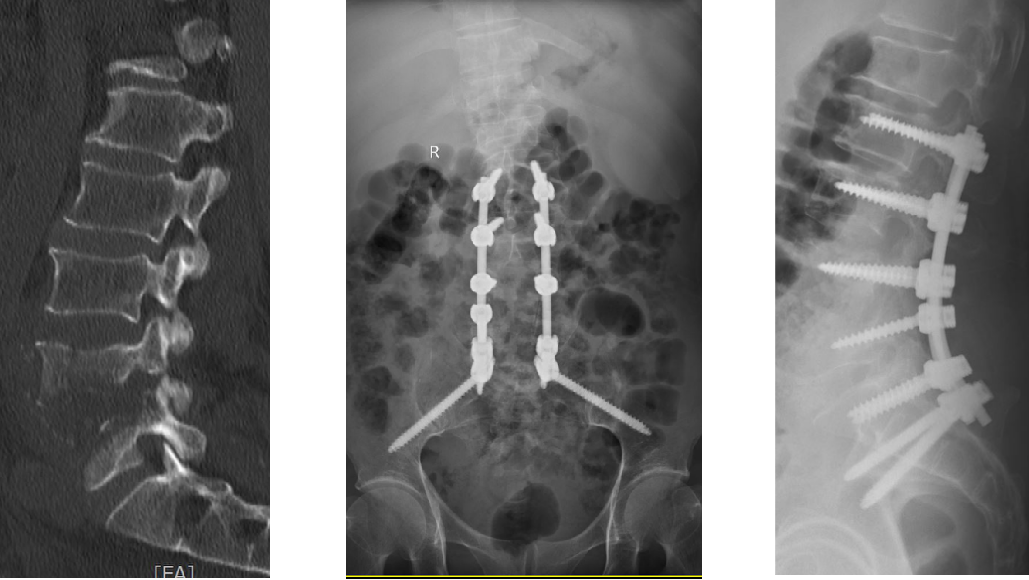

近日,绵阳市第三人民医院疼痛科·脊柱外科成功为一名腰椎骨质破环患者实施了骶2-髂骨(S2AI)螺钉内固定术,重建腰骶稳定性。

一切准备就绪,科主任杨启远带领医疗团队为唐先生实施了腰椎感染病灶清除+S2AI技术。2根长约8厘米的骶髂螺钉精准固定,在患者腰骶部起到底座支撑作用。

置入两根这么长的钉子,对手术医生来说,是很大的挑战。人体的腰骶部位应力较高,腰骶部融合概率下降,如果植入位置不精准,有可能损伤髂内血管,导致致命性大出血和损伤神经,因此手术难度极大,需要丰富的临床手术经验以及对新技术的熟练掌握。

杨启远团队仔细研究术前影像学资料的基础上,精准实施了S2AI螺钉内固定技术,手术技巧娴熟,标志着疼痛科·脊柱外科技术水平已达省内先进,为复杂疑难的结构性脊柱不稳和畸形技术开展提供了最有力的技术支撑,也为疼痛科·脊柱外科技术的进一步发展奠定了良好的基础。